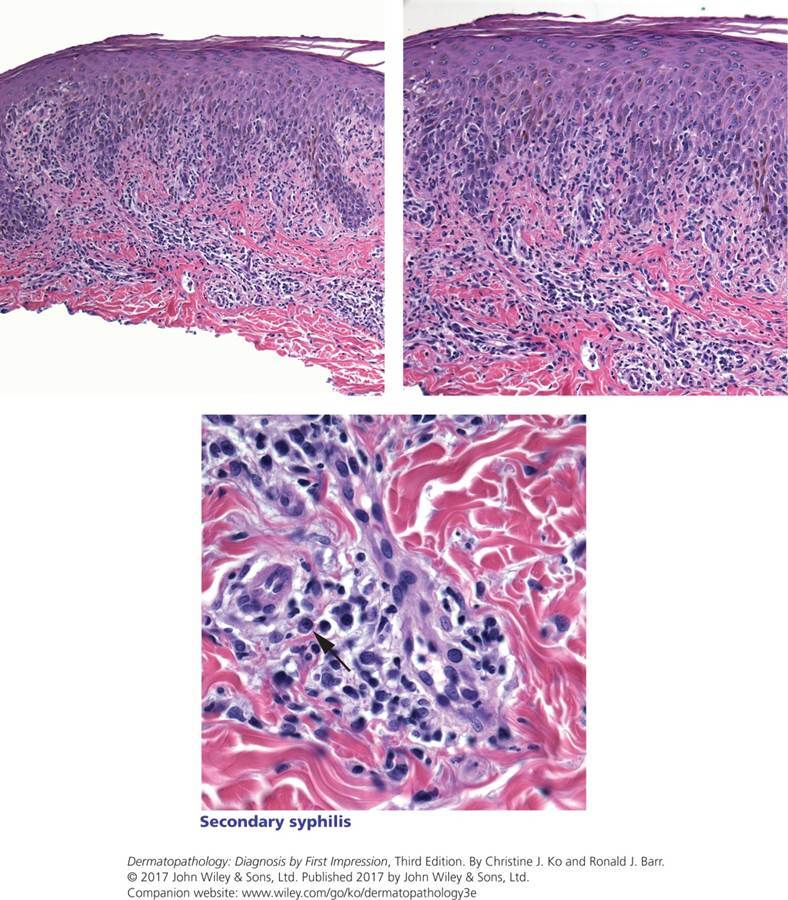

Syphilis